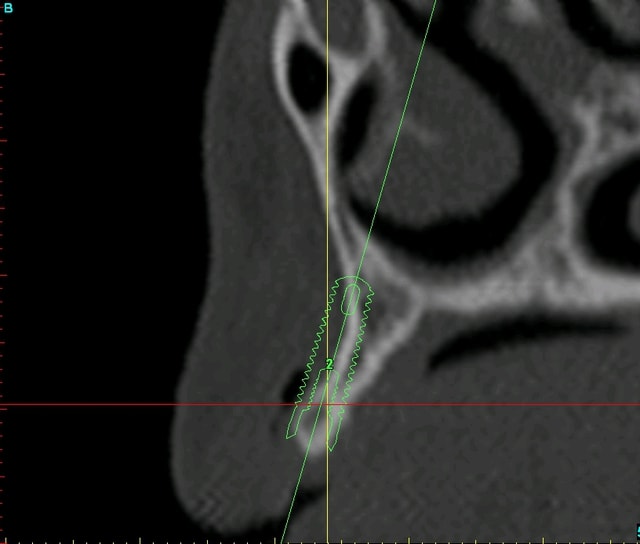

bon, pour que vous puissiez estimer l'ampleur du travail, je vous poste les coupes scan et les photos de la réplique plastique...;-)

quand on voit mes doigts sur les photos, on se rend mieux compte de la minuscule bouche de cette patiente (et je n'ai pas des mains de charretier!!!)

12 xfdtph - Eugenol

13 xpkert - Eugenol

23 wflnz5 - Eugenol